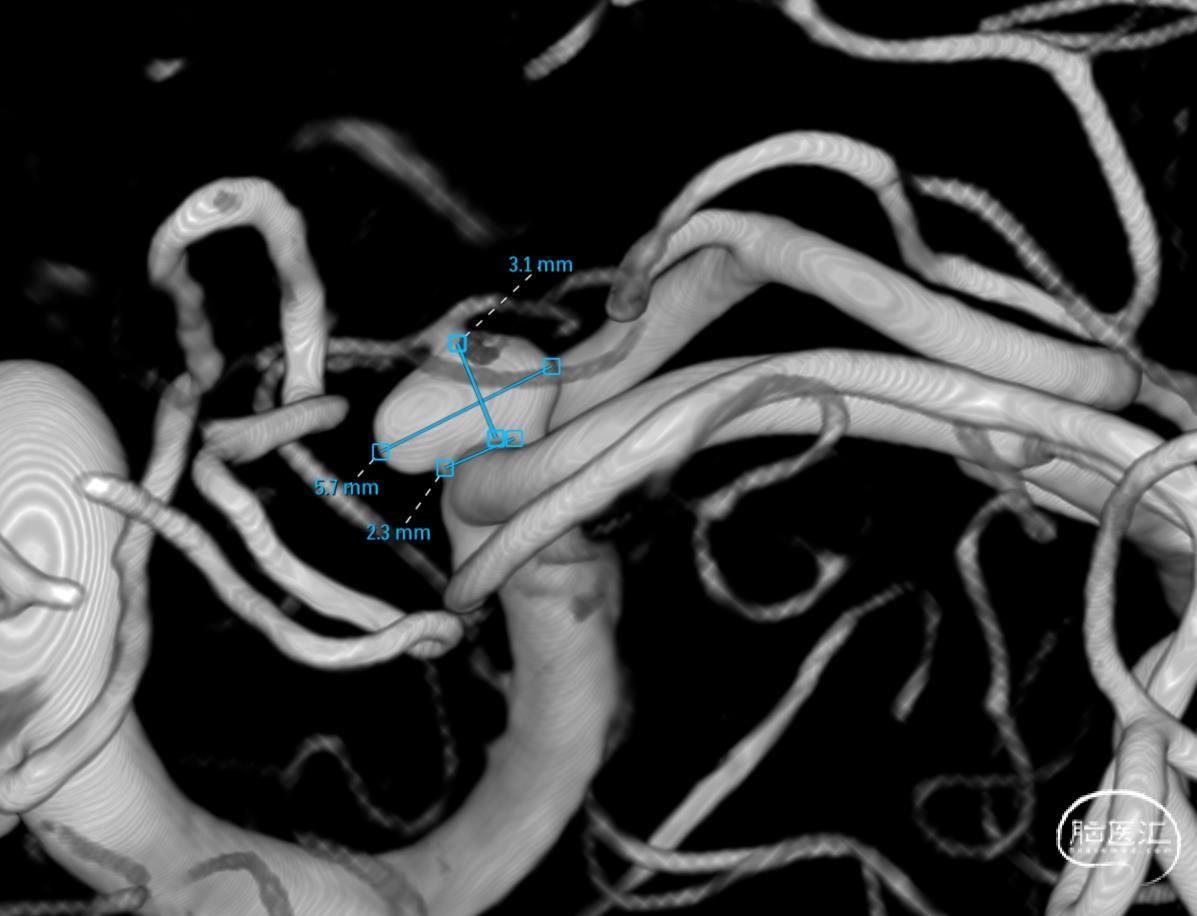

3D-RA成像

动脉瘤位于M1分叉处,三分支。

难点:绝对宽颈,分支需要保护,支架辅助栓塞,可能需要Y支架保护分支。

M1分叉处动脉瘤的病例,M1与M2多有成角,且角度较大,这是本例的另一个难点。本例在操作时,仔细评估图像,对微导管、微导丝充分塑形,在对Synchro导丝塑形的基础上,对微导管头端也进行了J形塑形,保证了支架导管的顺利到位。